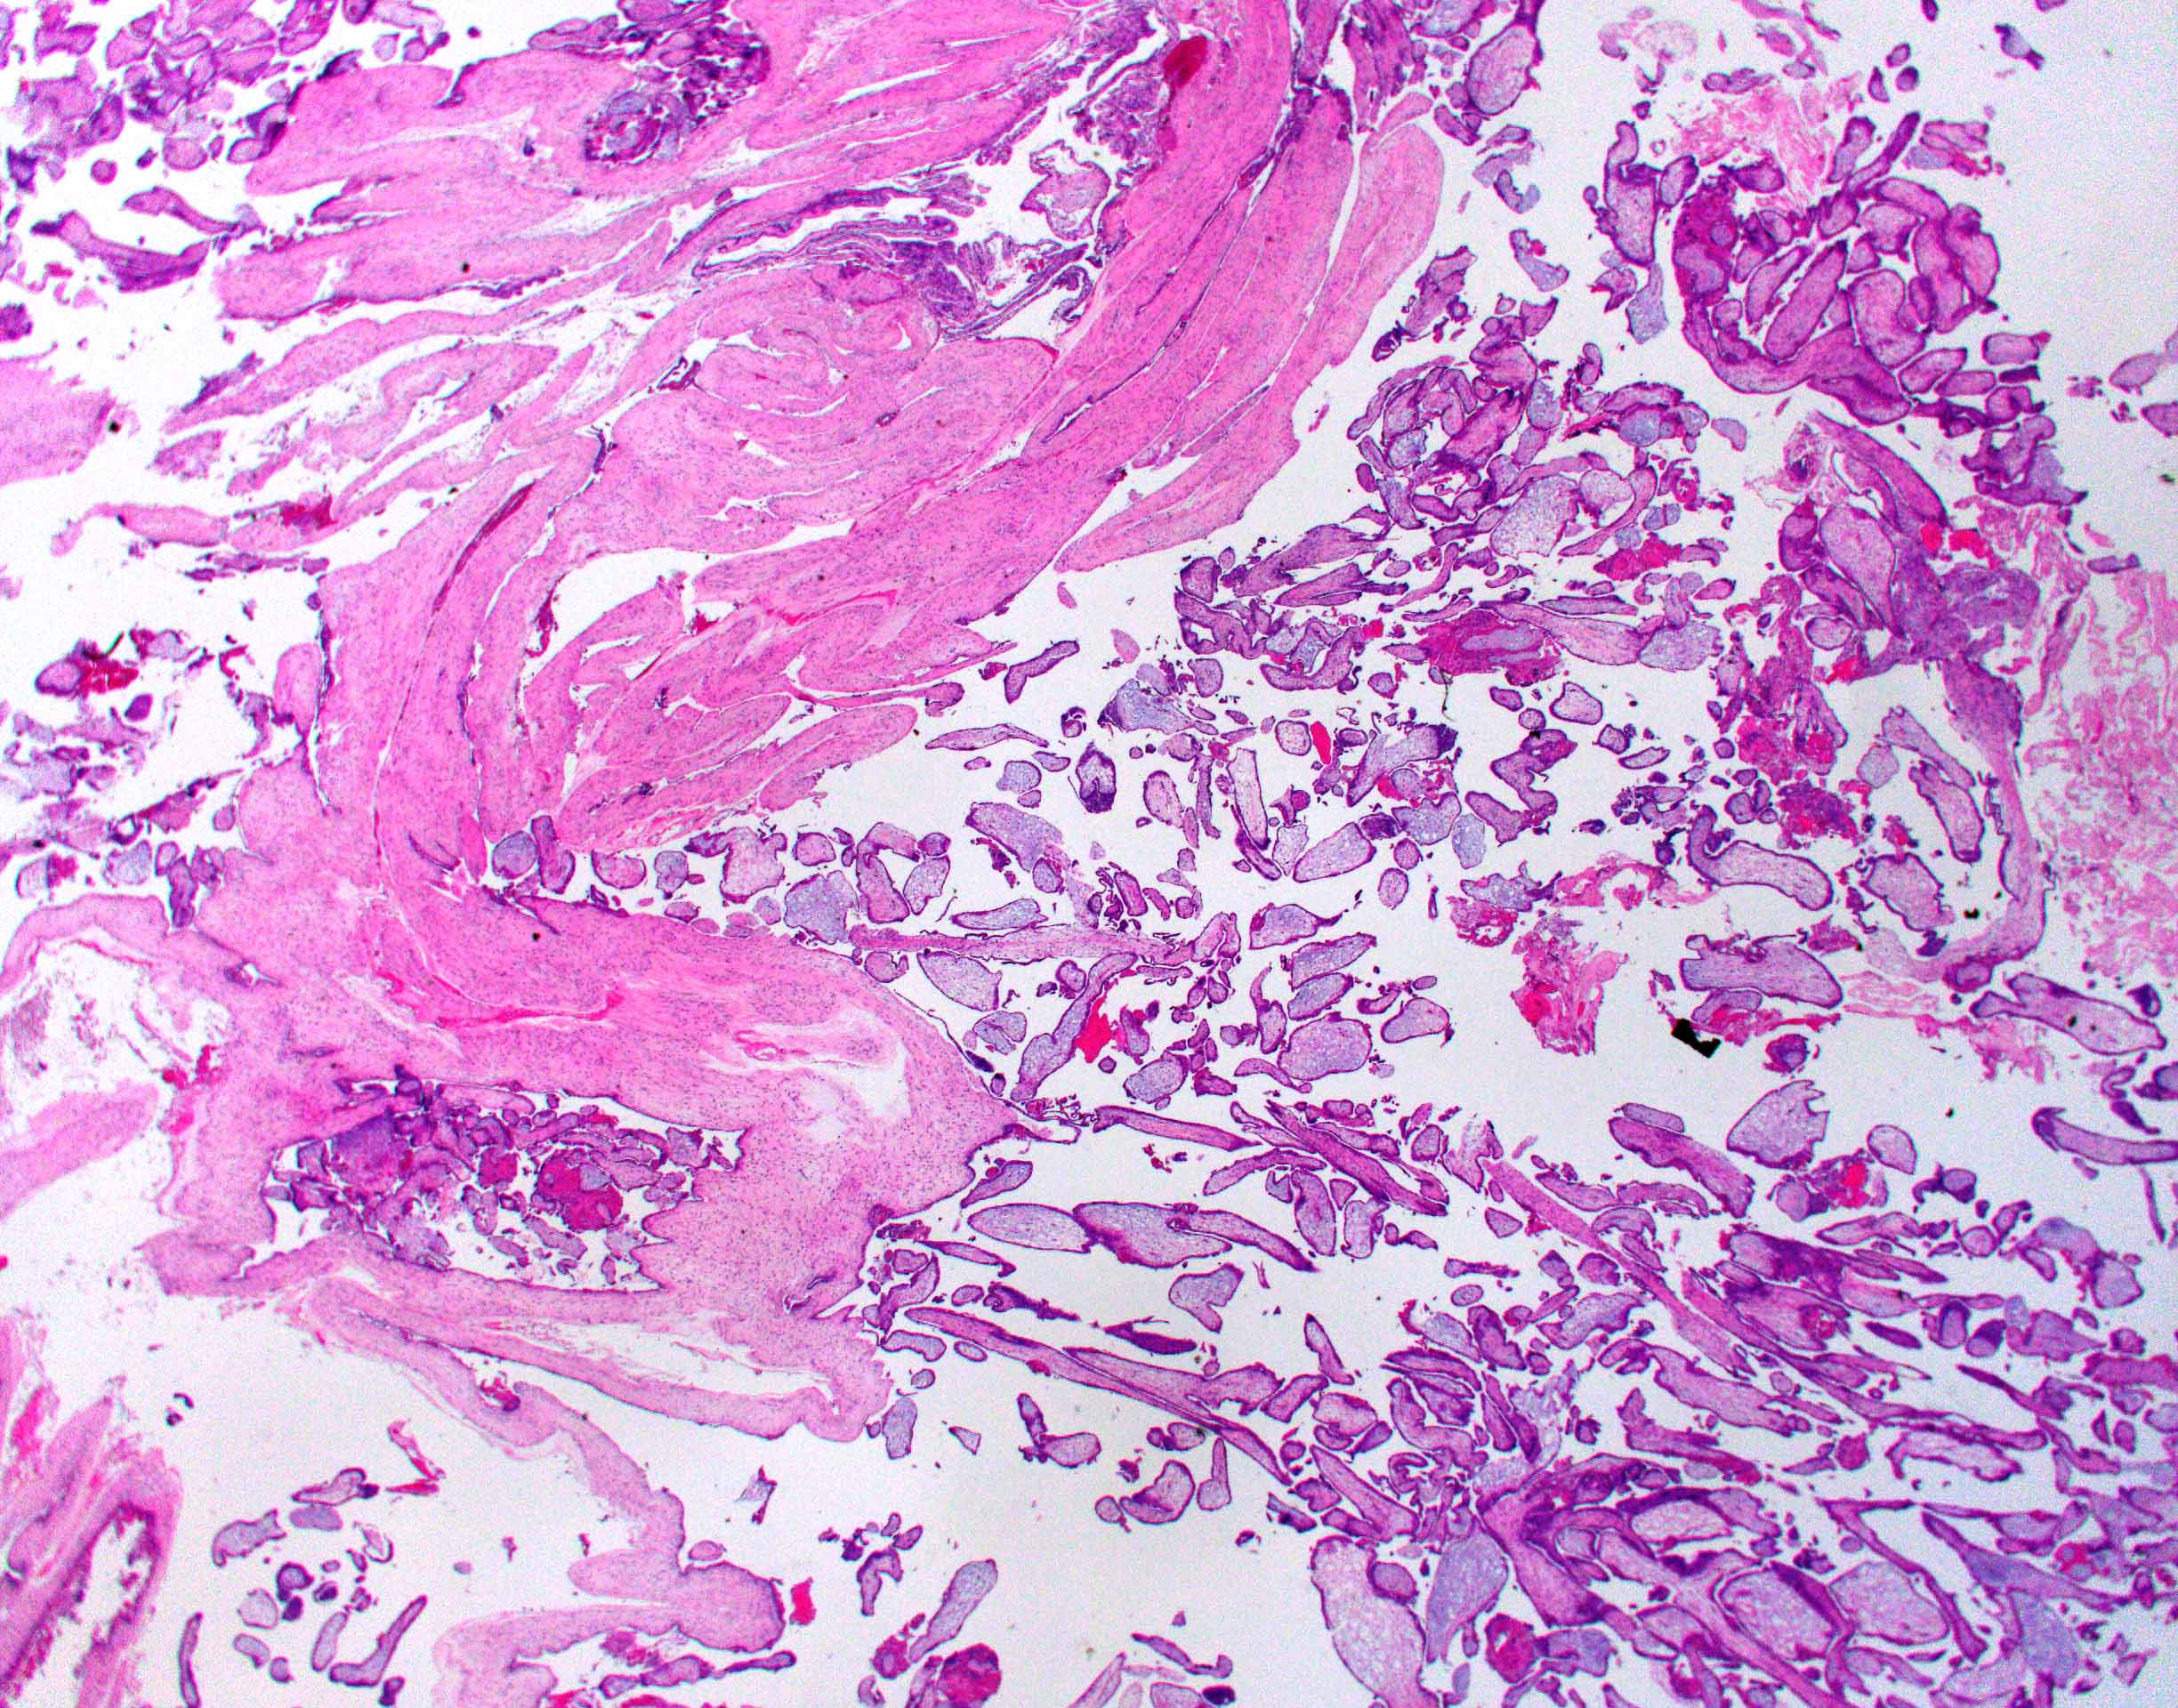

Microscopic (histologic) description

- Removed or passed products of conception may contain:

- Early first trimester chorionic sac (< 8 weeks): thin chorion and scant villi that are sparsely or nonvascularized

- Villous trophoblast is bilayered (mononuclear cytotrophoblast inner layer and multinucleated syncytiotrophoblast outer later) and circumferential with occasional polarized trophoblast protrusions

- Mid first trimester chorionic sac (8 - 10 weeks): may exhibit recognizable amnion, early stromal collagenization of chorion and proximal villi and increased volume of distal villi with distinct capillaries

- Later first trimester chorionic sac (> 10 weeks): may exhibit loose fusion of amnion and chorion, a more collagenized chorion and stem villi, more distinct walls of fetal vessels and numerous villi with increasing demarcation between proximal and distal branches

- Spectrum of villous changes in immature chorionic villi following embryonic death (Placenta 2005;26:114):

- Cellular debris within villous vessels - earliest change

- Villous edema with myxoid stromal degeneration - may be confused with molar gestation

- Collagenized avascular villi (villous sclerosis / fibrosis)

- Villous edema and sclerosis / fibrosis often coexist

- Other findings: prominent perivillous fibrin with prolonged retention or in medical abortions, otherwise pathologic

Microscopic (histologic) images

Contributed by Chrystalle Katte Carreon, M.D. and Drucilla J. Roberts, M.D.